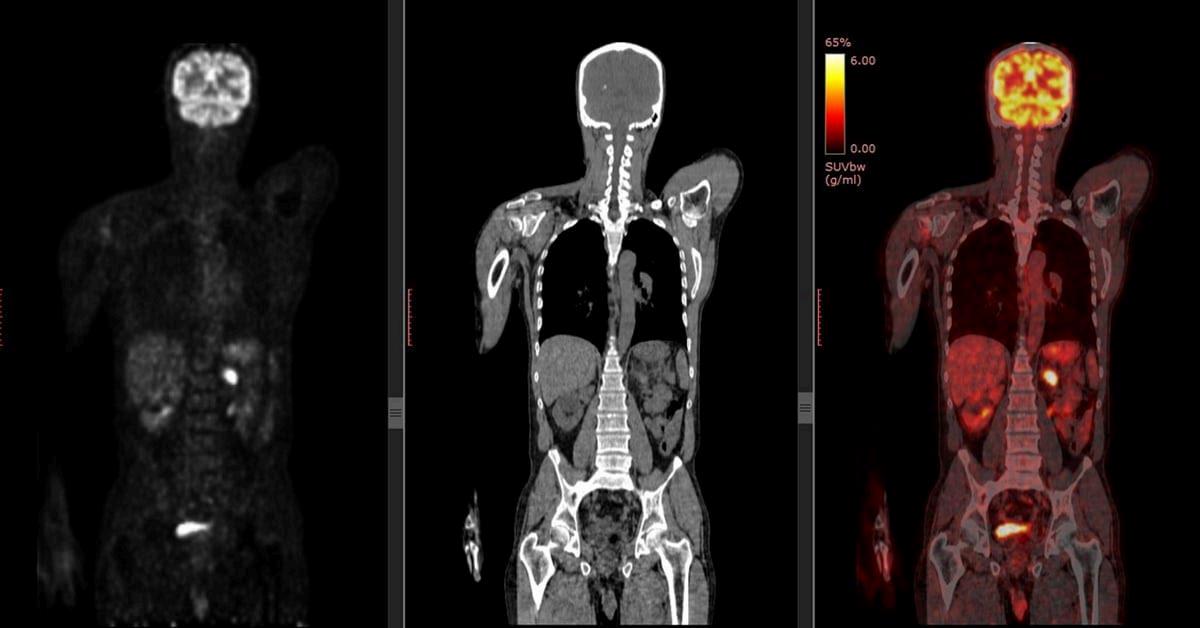

Tomografíaporemisióndepositrones-tomografíacomputarizada:moderadacaptacióndifusaen ambasglándulasparótidassugerentedeprocesoinflamatorio,infeccioso,autoinmune,etc.Presenta adenopatíaslaterocervicalderechaymediastínicashipermetabólicas,bajacaptacióndifusaenambos parénquimaspulmonaresyesplenomegaliaconincrementometabólicodifuso,todoellosugerentede procesoreactivo/inflamatorio.Haydisminucióndelacaptaciónrenalbilateralcompatiblecon insuficienciarenal.Nohayotroshallazgosindicativosdelesionesneoplásicas.

Tomografíaporemisiónde positrones.(tomografía computarizada)

Esunapruebamedianteimágenesque puedenayudararevelarlafunción metabólicaobioquímicadelostejidos yórganos

Estapruebautilizaunmedicamento radiactivo,quemuestralaactividad metabólicatípicayatípicadetectando laradiación.